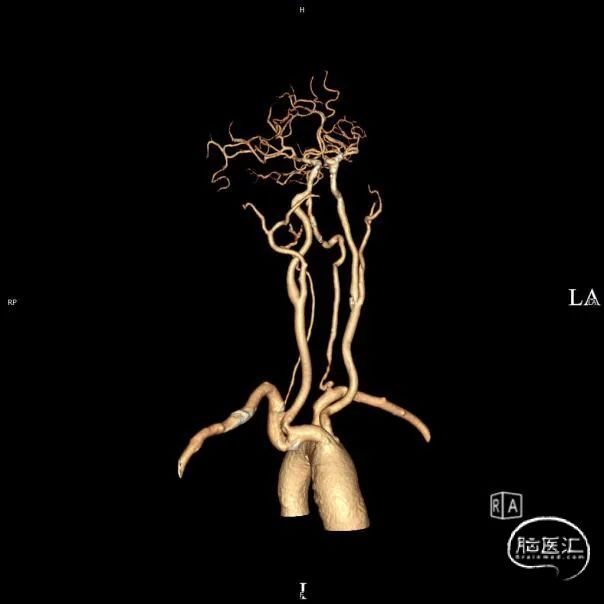

➢头颈部CTA(三维重建MIP像)

➢头颈部CTA(原始像)

患者于入院前10天突发视物重影,5分钟左右缓解,当晚18:00出现颈后不适伴左上肢持续性麻木,10天后来我院急诊神经内科就诊,就诊时测血压191/93mmHg,自行服用拜新同1粒。 完善头颅MRI:桥脑、两侧小脑急性缺血性梗塞;右侧基底节软化灶;两侧侧脑室旁少量白质疏松;老年脑改变。 入院后予药物保守并完善头颈部CTA:左侧颈内动脉虹吸段多发钙化斑块、混合斑块,管腔轻-中度狭窄,C7段小动脉瘤。右侧颈内动脉虹吸段多发钙化斑块,管腔轻度狭窄。右侧椎动脉纤细,V4段局部显示欠清。左椎V1、V2段非钙化斑块,局部管腔重度狭窄-闭塞,V4段钙化斑块,管腔中度狭窄。右侧部分型大脑后动脉,P1段重度狭窄,P2段中度狭窄。双侧大脑中动脉M2段中至重度狭窄。 告知患者病情存在进一步进展可能,患者家属商量后要求手术治疗。

术前影像考虑右侧孤立椎,左侧椎动脉V1段重度狭窄、狭窄段以远扭曲成襻且合并长节段多发动脉粥样硬化狭窄改变(夹层待排),同时左椎V4段局部重度狭窄可能;